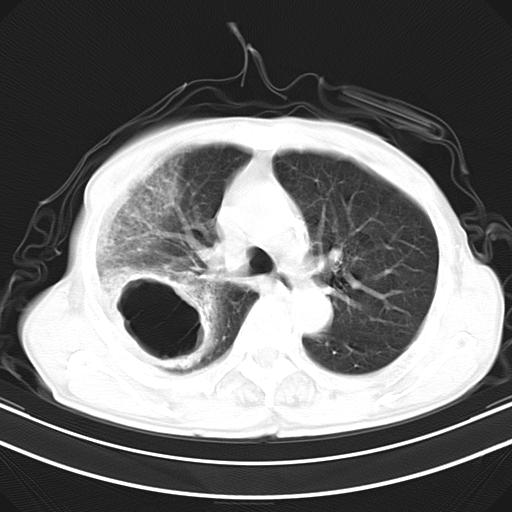

标题: CT23873:男,70,发烧咳嗽咳痰10余天,查痰结核菌阴性 [打印本页]

男,70,发烧咳嗽咳痰10余天,查痰结核菌阴性。否认以前有肺病史。治疗10天后症状减轻。 img]/upload/forum/2009/12/302117469692.jpg[/img]

影像所见:右上肺见一巨大厚壁空洞,内壁欠光整,右上肺广泛斑片状、大片状模糊阴影。

影像所见:右上肺见一巨大厚壁空洞,并见分隔,内壁欠光整,右上肺广泛斑片状、大片状磨玻璃阴影。